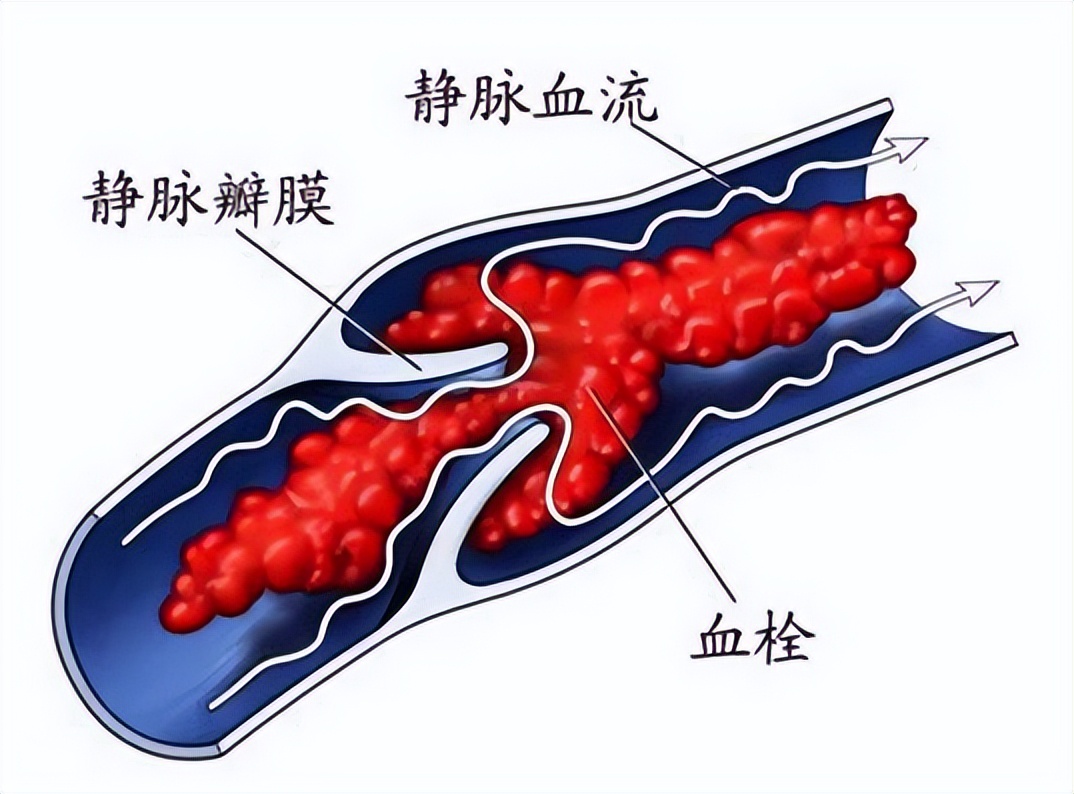

祖国医学中并无“血液高凝状态”之病名,部分学者根据其发病特点及临证表现常常把其归为“股肿、脉痹”范畴,骨科大手术术后并发血液高凝状态或者DVT其根本病机为气滞血瘀湿阻,或兼夹气虚或兼夹血虚。

《灵枢·经脉》云:“脉道以通,血气乃行”,脊柱椎体骨折局部椎体骨质骨断筋离、经脉损伤进而血溢脉外、气机逆乱,此使机体呈现出血瘀之征象,症见腰背部刺痛,舌暗红有瘀点,脉弦涩或弦滑;此外加之手术二次创伤,筋脉再次受损导致血溢脉外,气血运行不畅,进而继续加重血瘀之征象。

气为血之帅,血为气之母;骨科术中失血耗气、术后卧床伤气;根据气血之间的关系,气血相互影响,气虚则运血无力,血虚则气生化乏源,最终导致血瘀与气血虚互相影响,致使机体出现血瘀夹气血两虚等表现。

筋脉损伤、久病卧床为此病两大病因。因此针对于脊柱骨折术后早期多出现气滞血瘀之症,随着卧床日久继而出现血瘀夹虚之证候,临床多以活血化瘀兼顾益气活血为其主要治则。

通过研究复元活血汤与单纯物理预防对脊柱骨伤术后血液高凝状态的影响,进行随机对照试验,发现中药组D-Dmer值明显低于单纯物理预防组,具有显著差异,提示复元活血汤可降低术后DVT的发生,改善血液高凝状态。

通过分析中医药预防骨科术后DVT的相关文献,得出活血化瘀法可以有效降低的DVT发生率的结论,其基础方主要为桃红四物汤。益气活血法:传统医学多认为年老多虚,久卧伤气。

气为血之帅,因而对于骨科手术或者卧床日久患者,多伴有气虚夹瘀症状,针对骨科术后气虚血瘀之症,预防VTE多采用益气活血之法。

研究发现采用益气活血之法干预,可有效降低临床术后患者血栓发生率,表明益气活血之法在气虚血瘀之症中预防VTE是行之有效的,并且期间未发生毒副反应进一步证明具有相对安全性。

上述动物实验都表明身痛逐瘀汤可以基于改善血液高凝状态,继而减少DVT的发生率。与此同时,大量临床试验也表明身痛逐瘀汤可以改善骨科术后凝血功能及血液高粘、高凝状态,进而较少DVT发生率。

通过对43例膝关节单髁置换术后随机对照临床试验,试验组予以利伐沙班联合身痛逐瘀汤口服,对照组予以单纯利伐沙班抗凝治疗,监测两组凝血功能及D-二聚体及血小板等相关指标,结果提示身痛逐瘀汤在发挥抗凝作用的同时不增加出血风险,可有效改善血液高凝状态,降低血栓发生率。

基于祖国医学辨证论治的基础,脊柱骨折术后早期血液高凝状态多属于气滞血瘀之证,又因近现代大量动物、临床试验研究及文献支持提示身痛逐瘀汤具有抗凝、改善骨科术后血液高凝状态及降低DVT发生率的作用,因此根据祖国医学异病同治理论,本研究选用身痛逐瘀汤加味可行。